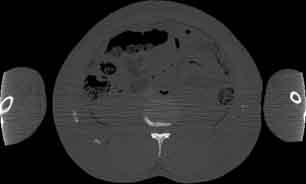

Visible Human male: Sectio transversalis 1652

CT

NMR

Pd                          / T2 \                         T1